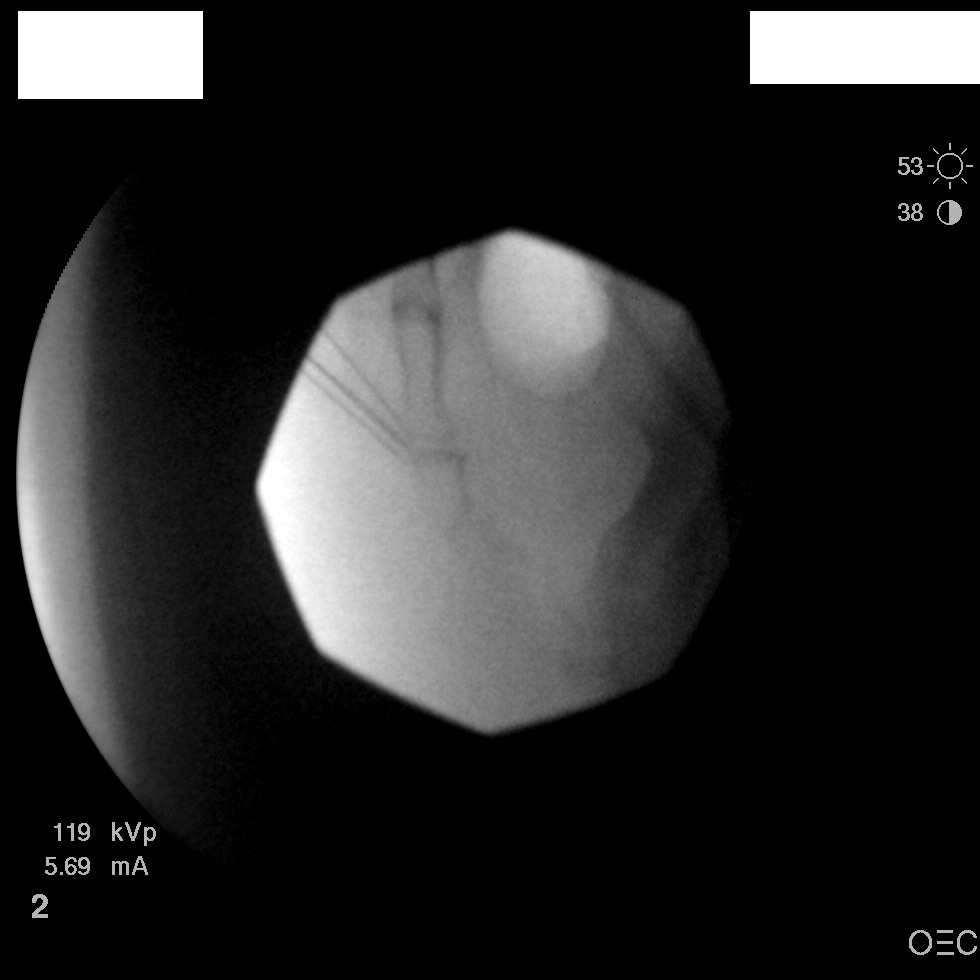

I have a patient with several months of coccyx pain. Worse with sitting, TTP over coccyx. Otherwise normal exam. No trauma, but she has an anteriorly displaced coccyx. Failed NSAIDs and no one around me does good pelvic floor PT. I scheduled her for ganglion impar injection, but her insurance won't pay for it. They wouldn't even let me to a peer-to-peer... they just straight up said they won't cover it. Any other treatment options? I don't want to send her to a surgeon. Thanks.